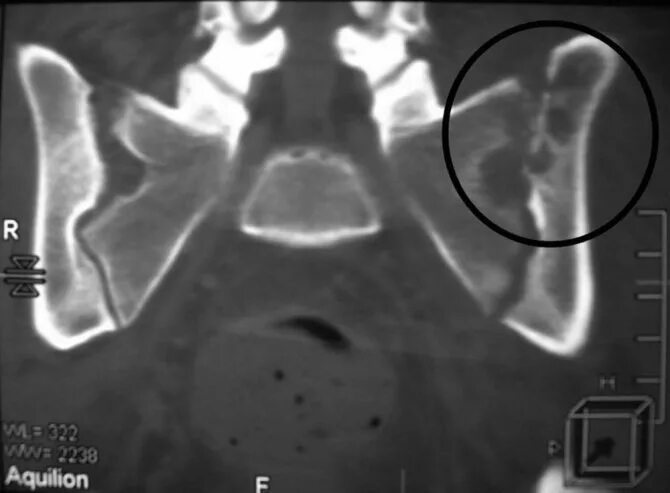

Метастазы в крестце